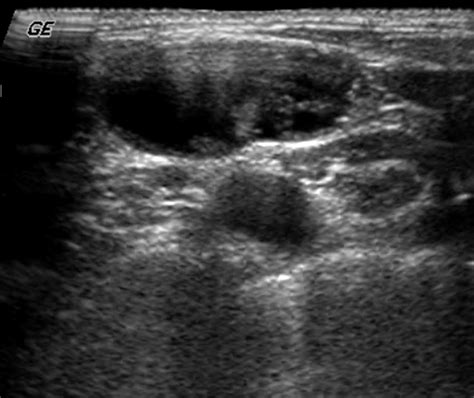

• Size and Shape: Normal nodes are typically oval, whereas malignant nodes may appear more rounded or spherical.

• Internal Architecture: Healthy nodes have a clear, bright central area called the “fatty hilum.” The absence of this hilum can be a warning sign.

• Border Definition: Clear, regular borders are generally reassuring, while irregular or “matted” borders may warrant biopsy.

Internal Echo Homogeneous Heterogeneous (Mixed)